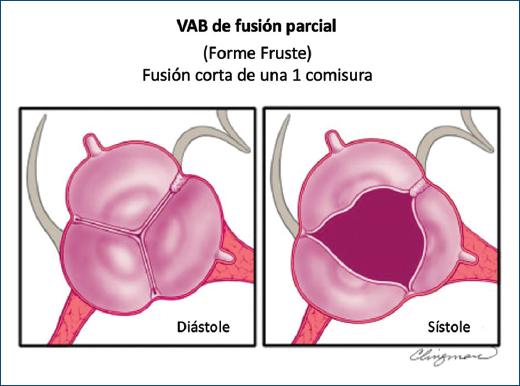

LA VÁLVULA AÓRTICA BICÚSPIDE DE TIPO FUSIÓN PARCIAL (O FORME FRUSTE)

Se desconoce la prevalencia de este tipo de VAB de fusión parcial recientemente descrito (o VAB forme fruste [forma frustrada])45 (Fig. 13). La apariencia de la VAB de fusión parcial es la de una válvula aórtica tricúspide típica con tres cúspides simétricas con una apertura triangular sistólica y ángulos comisurales de 120°, sin embargo en la inspección quirúrgica o la imagen de alta resolución se observa menos del 50% de fusión entre dos cúspides en la base de una comisura, formando un pequeño «minirafé»6,45-47. Es importante reconocer y seguir estudiando la VAB de fusión parcial, que se ha descrito con mayor frecuencia en el quirófano en pacientes sometidos a cirugía por dilatación aórtica45 (Fig. 14)47. Esta VAB forme fruste resulta en la alteración de los patrones de flujo aórtico, que consiste en un aumento de la excentricidad del flujo y un aumento de los vórtices46, quizás explicando parcialmente la aparente alta prevalencia de dilatación aórtica en estos pacientes. Referirse a este fenotipo como VAB de fusión parcial o VAB forme fruste es apropiado, al igual que señalar entre qué cúspides se produce la fusión: derecha-izquierda, derecha-no coronariana y así sucesivamente.

Figura 13 Esquema del fenotipo de la válvula aórtica bicúspide de fusión parcial visto en la proyección del eje corto paraesternal del ecocardiograma transtorácico. Panel izquierdo. La apariencia en diástole de la válvula aórtica bicúspide de fusión parcial o forme fruste (forma frustrada) es la de una válvula aórtica tricúspide. Panel derecho. El diagnóstico por imágenes generalmente se realiza en sístole. Aunque la apertura parece triangular, hay una pequeña fusión de las cúspides derecha e izquierda con un «minirafé». Estos pueden sospecharse mediante ecocardiograma transtorácico o transesofágico, y confirmarse mediante un ecocardiograma transesofágico tridimensional, resonancia magnética cardiaca o tomografía computarizada cardiaca. La confirmación definitiva generalmente se realiza mediante inspección quirúrgica o análisis patológico (modificada de Michelena et al., 20206 con permiso de Elsevier).